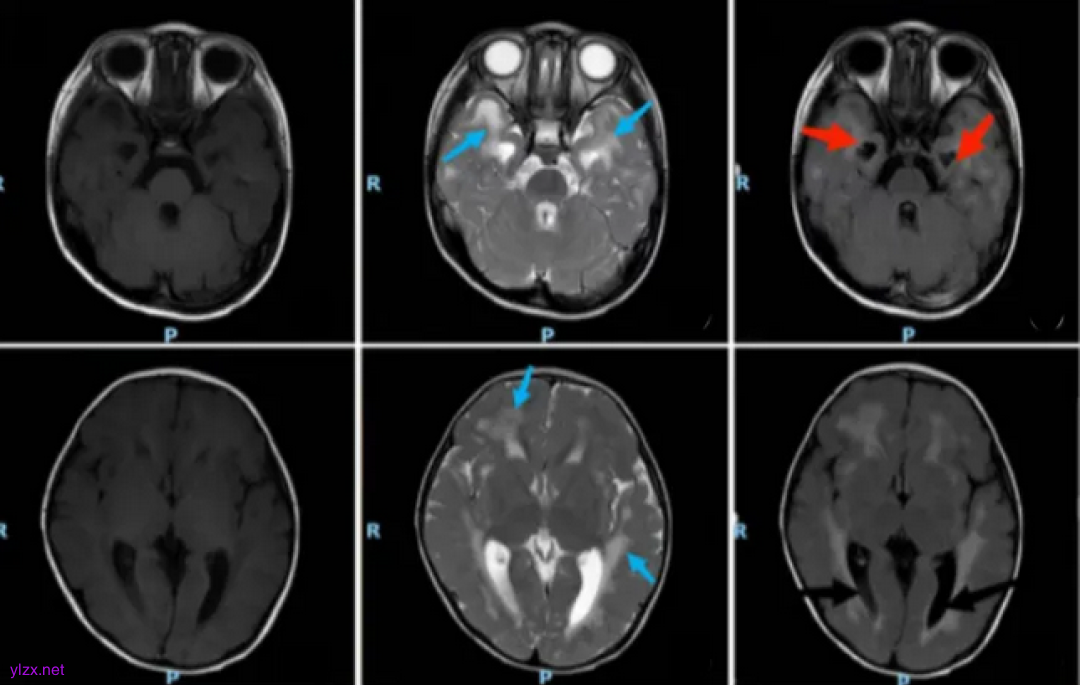

接诊医生详细了解了患儿的病史、临床表现及检查结果,仔细查看了孩子的病情,从这10年的病史中抽丝剥茧。根据孩子双下肢肌力降低、皮疹、颅内钙化等表现,结合患儿IFIH1基因突变的致病性分析,均可用IFIH1基因突变导致的AGS综合征来解释。

患者头颅MRI

AGS综合征神经系统表现为:颅内多发钙化灶、脑白质病变、脑脊液慢性淋巴细胞增多。